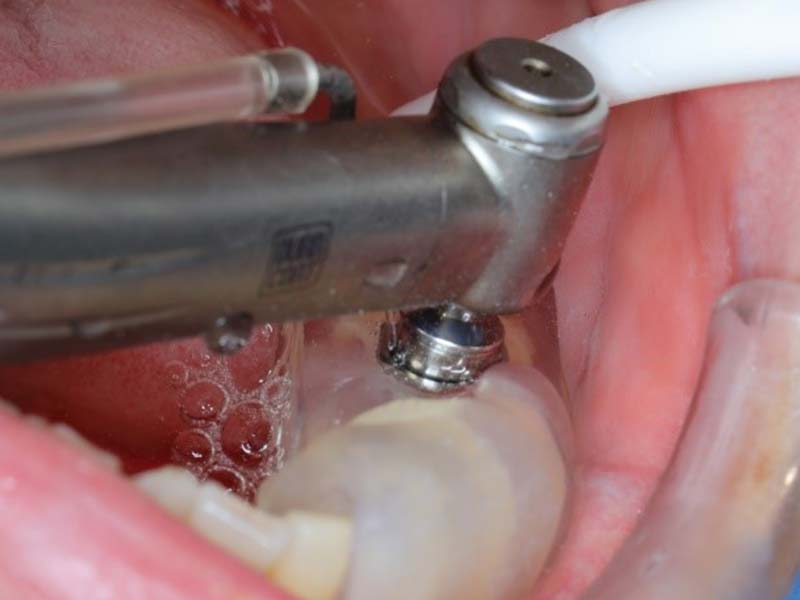

2.可進行微創植牙手術

不同於一般植牙手術,微創植牙手術不須切開牙齦再縫合。傷口小、出血量少,疼痛感比傳統植牙手術減輕許多,復原時間也相對縮短。減輕疼痛及發炎,降低感染風險,精準且舒適,為最新一代植牙技術。